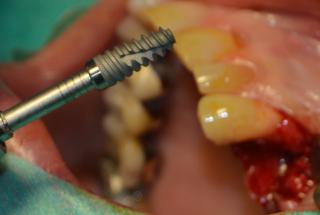

Clinical cases

MPI closely monitors clinical cases in the market to ensure their correct functioning and successful outcome.